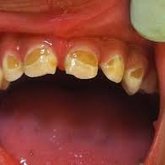

We make it a priority to incorporate the latest in dental technology in everything we do at our practice. ...